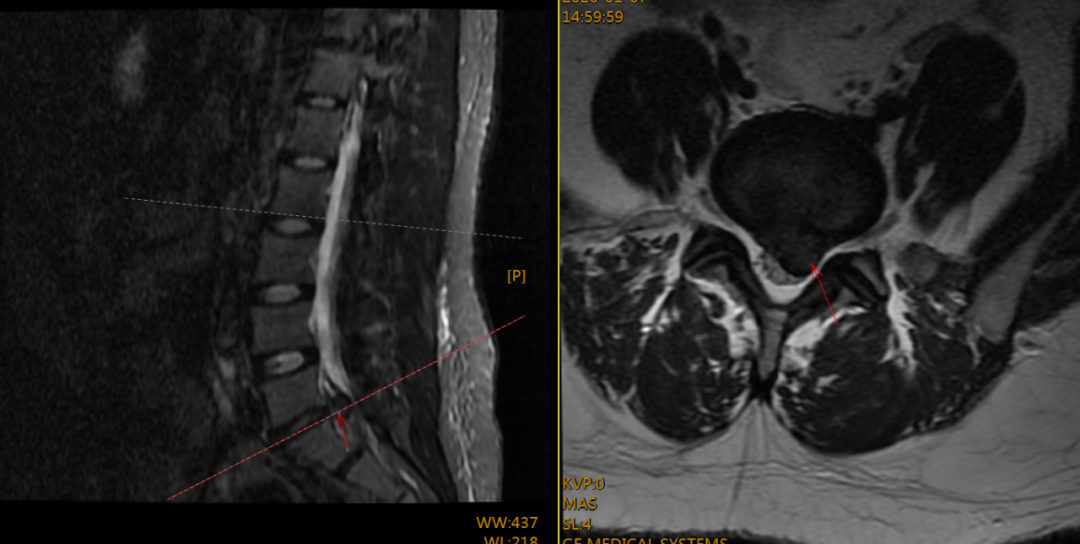

入院后,专科检查显示左下肢直腿抬高试验及加强试验在30度即呈阳性,是神经根受到牵拉刺激的明确体征。结合腰椎核磁共振(MRI)这一“金标准”影像学检查,清晰显示腰5-骶1节段左侧椎间盘突出,并压迫到左侧神经根,诊断明确。对于经系统保守治疗,如休息、药物治疗、康复理疗等无效,或症状严重、出现神经功能损害迹象的患者,手术干预是解除压迫、根治症状的有效手段。

术前腰椎MRI平扫示间盘CT示腰5-骶1椎间盘左侧突出,压迫左侧神经根